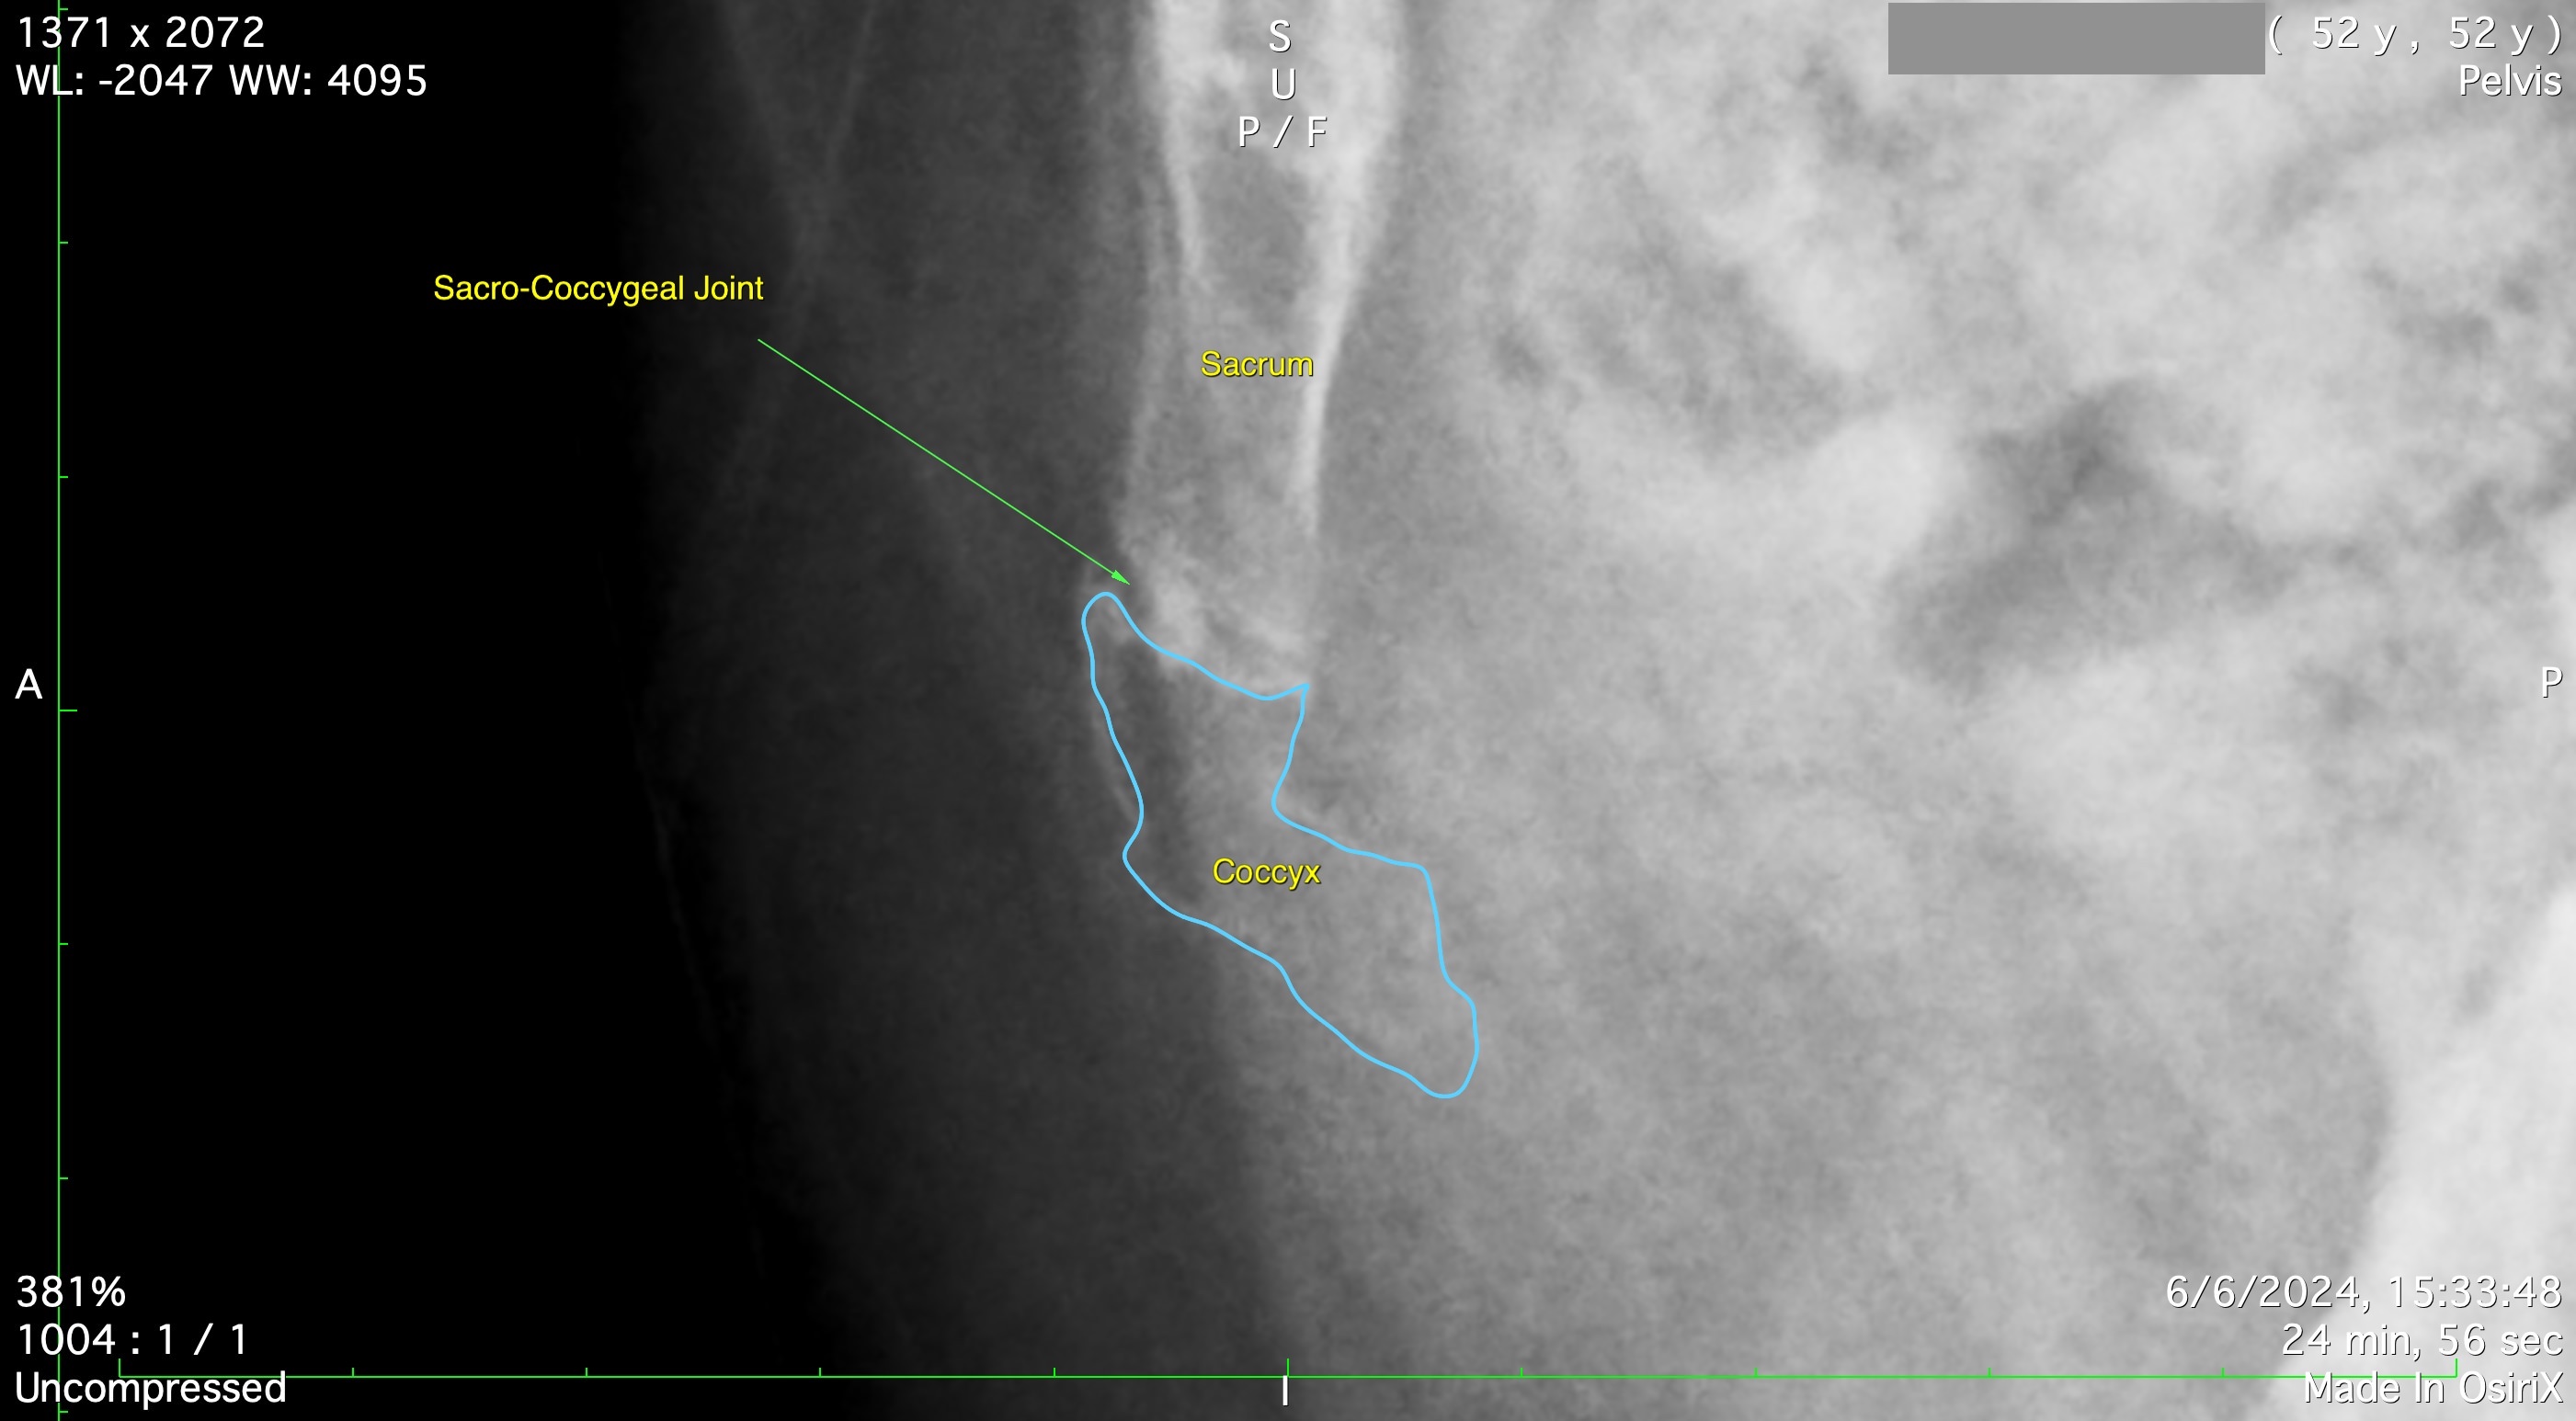

X-rays and other imaging studies do not reliably demonstrate ‘primary idiopathic coccydynia’ but may be conducted to exclude other – potentially serious – conditions that can cause similar symptoms. It can be difficult to see the coccyx clearly on X-ray.

Fig 1. X-ray can be difficult to interpret.

Sitting X-rays (see Figures 1 & 2) can be helpful.

Fig 3. Seated lateral coccyx radiograph.

X-ray and MRI may demonstrate tumours, infection, crystal deposition, and cystic formations such as a pilonidal cyst [3].

A CT scan is helpful in patients who have persistent symptoms despite first-line (physiotherapy) treatment, in order to help guide injections.

CT gives very high definition images of the bones, and can usually show if any given joint is fused or mobile (Figure 4)

Fig 4. CT coccyx shows bones in detail. This patient has only one joint – between Cx 1 and Cx 2. The sacro-coccygeal joint is fused.